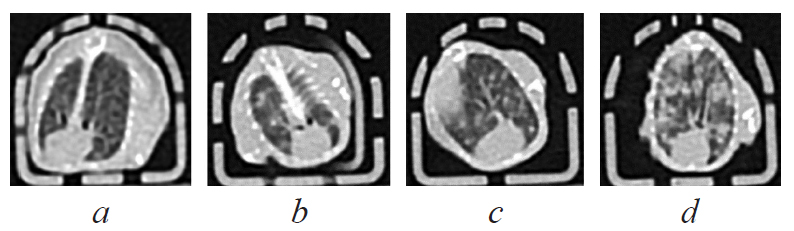

По данным компьютерной томографии инфильтративно-очаговые изменения в легких регистрировали во 2-й и 4-й группах у всех мышей, начиная с 14-х суток эксперимента. В группе контроля опухоли очаговые изменения в легких выявлялись на 14-е сутки у трети, а на 21 сутки — у всех исследованных животных. Примеры компьютерных томограмм легких представлены на рис. 2.

Рис. 2. Компьютерные томограммы легких мышей линии C57BL/6: a — легкие интактного животного (группа 1), b — туберкулезный инфильтрат в верхней трети правого легкого (группа 2), c — метастатический очаг в нижней трети левого легкого (группа 3), d — субтотальная очаговая сливная инфильтрация в легких мыши (группа 4)

Fig. 2. Computed tomograms of the mice lungs: a — the lungs of an intact animal (group 1), b — tuberculous infiltration in the upper third of the right lung (group 2), c — metastatic focus in the lower third of the left lung (group 3), d — subtotal infiltration in the lungs of a mouse (group 4)

В нашем исследовании впервые был применен метод КТ для диагностики патологических изменений в легких у инфицированных МБТ животных и животных с трансплантированной опухолью, тогда как известно о его использовании для оценки динамики вирусной пневмонии у мышей [3]. Ранее для этой цели требовалось выведение части животных из эксперимента. Анализ компьютерных томограмм позволил дифференцировать очаговые метастатические и инфильтративно-очаговые воспалительные изменения в легких.